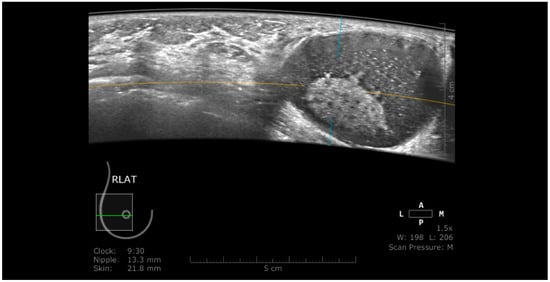

ABUS images are sectional and static images. This technical peculiarity opens the possibility to obtain false-positive results in complicated cysts mimicking complex cystic lesions. In these situations, HHUS may obviate in real-time the fact that the intracystic appearance is produced only by floating echoes (Figure 9).

Figure 9. Complicated cyst mimicking a complex cystic lesion using ABUS. Using HHUS, the intracystic component was proved to be only abundant, floating echoes.